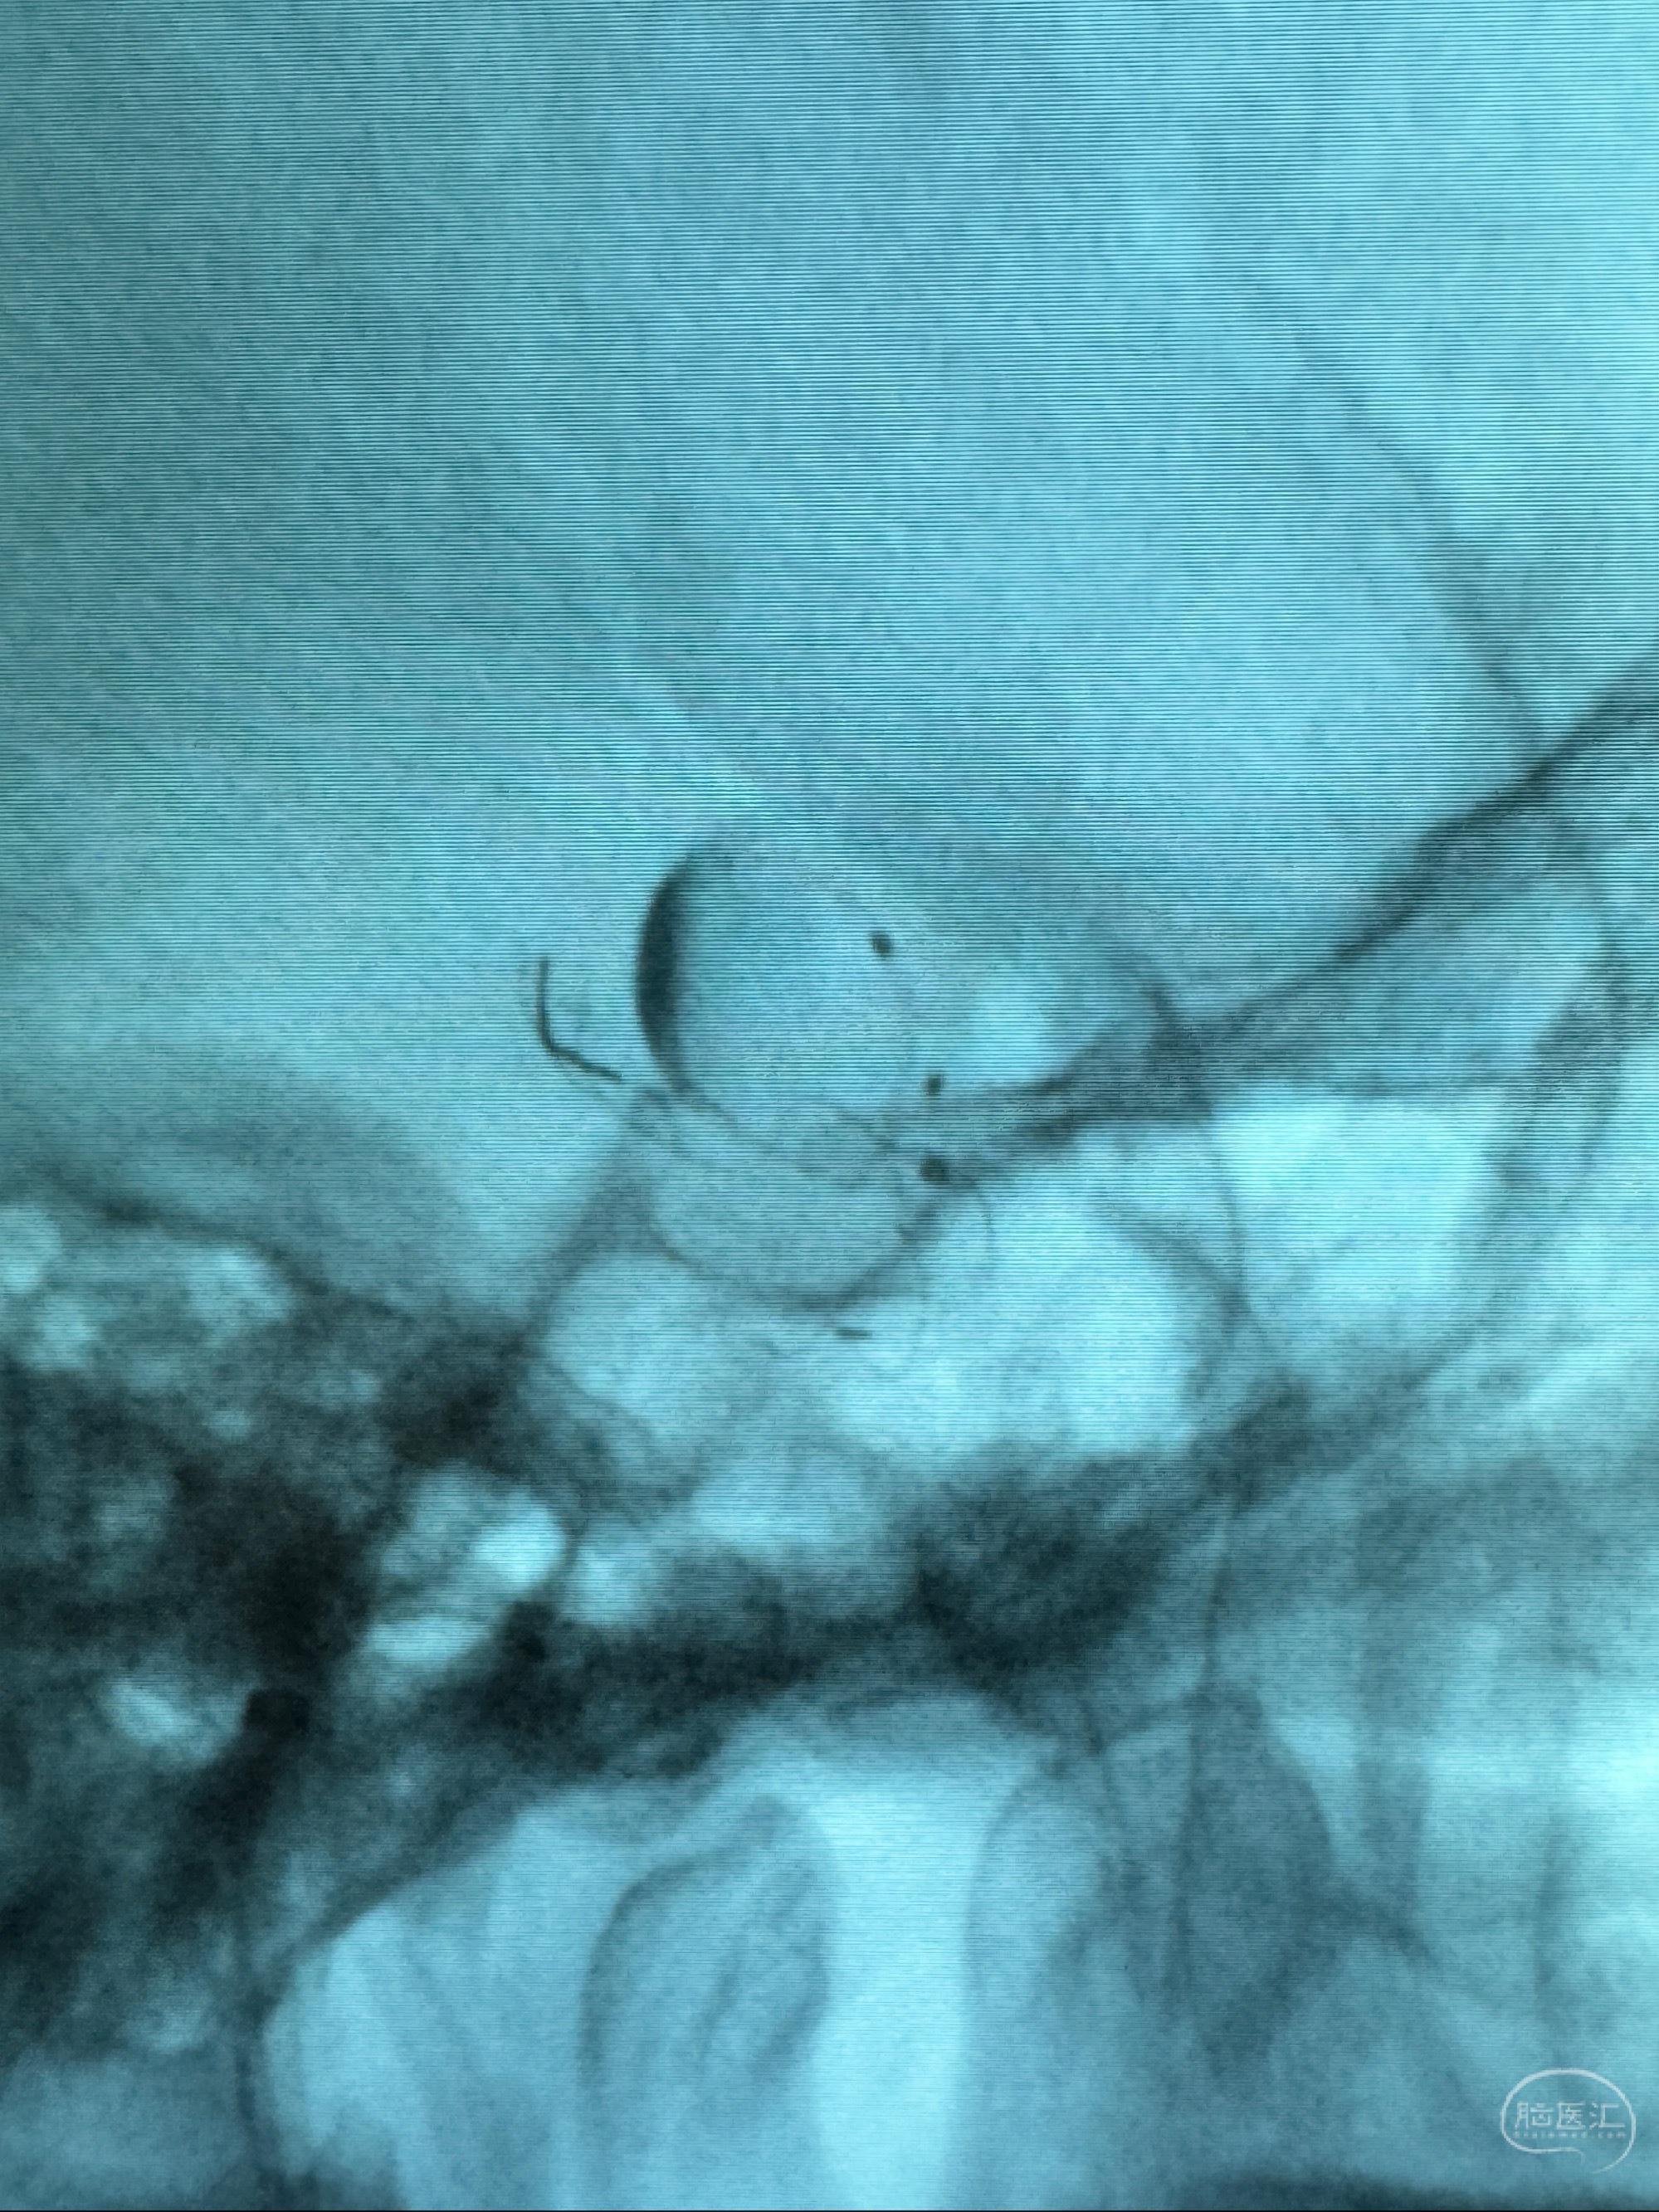

透视可见红圈部分为支架导管的头端

手推冒烟显示支架位置及展开情况,箭头为支架导管的位置